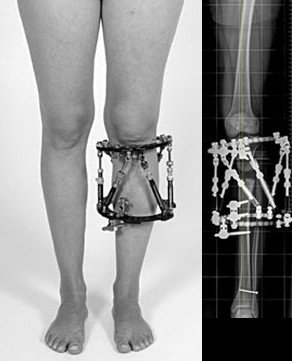

Therapie

Nach genauer Analyse der Deformität und Planung der Osteotomie wird der Taylor Spatial Frame am Unterschenkel fixiert und anschliessend der Knochen schonend durchtrennt. Anschliessend erfolgt eine langsame schrittweise Korrektur der Fehlstellung und die Knochenverlängerung.

Nach der Operation

Das klinische Ergebnis zeigt korrekte Achsenverhältnisse. Das Bein ist deutlich besser belastbar und das Risiko eines frühzeitigen Gelenkverschleisses ist minimiert.